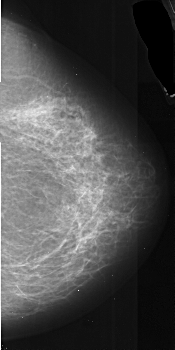

A_1036_1.LEFT_CC

RIGHT_CC LINES 5236 PIXELS_PER_LINE 2611 BITS_PER_PIXEL 16 RESOLUTION 42 NON_OVERLAY